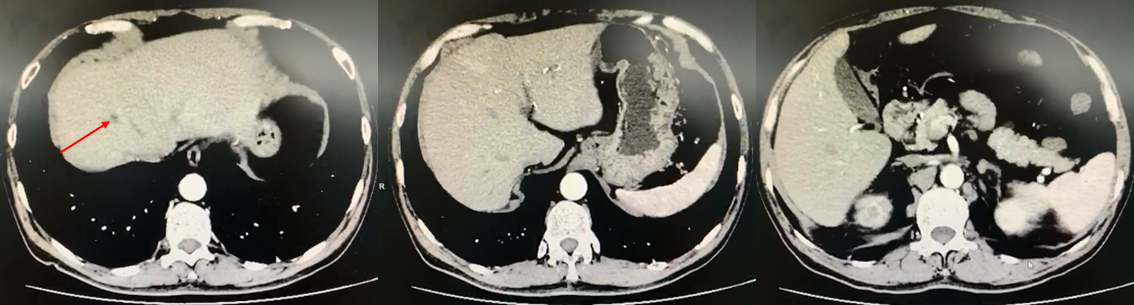

图3 患者肝脏及盆腔多发转移瘤(2019年1月25日)

2019年3月1日复查全腹部CT增强扫描示:肝及盆腔内多发转移瘤。对比2019.1.25前片,肝内部分病灶及盆腔病灶缩小(图4)。

图4 患者肝脏及盆腔转移瘤较前明显缩小(2019年3月1日)

2019-3-29复查全腹部CT增强示:肝脏及盆腔内多发转移瘤;对比2019.3.1前片,肝脏及盆腔转移瘤均明显缩小(图5)。后规律复查CT,表现基本相仿。

图5 患者肝脏及盆腔转移瘤继续缩小,疗效评估为部分缓解(PR;2019年3月29日)